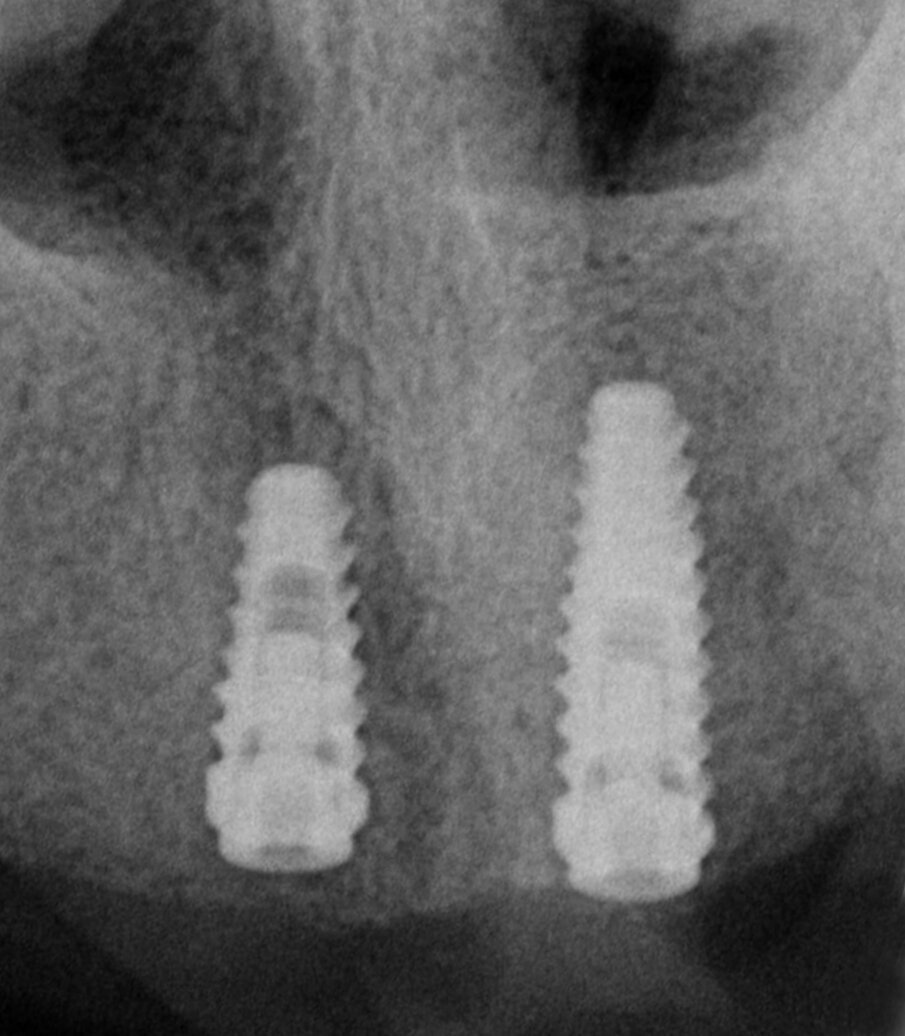

Una paziente di 62 anni, ASA 1 si rivolge alla nostra attenzione per richiedere una riabilitazione dell’arcata mascellare superiore essendo portatrice di protesi mobile totale. L’esame radiologico iniziale evidenzia una marcata atrofia ossea quindi viene progettato l’inserimento di 8 impianti dopo elevazione bilaterale dei seni mascellari al fine di realizzare un a protesi tipo Toronto-Bridge. Trascorsi 8 mesi dai sinus lift e dopo aver accertato la totale guarigione dei siti innestati con una CBCT viene eseguito l’intervento implantare in anestesia locale, sotto profilassi antibiotica, con chiusura dei lembi per prima intenzione e senza eseguire procedure di carico immediato. La paziente viene quindi controllata regolarmente ed a distanza di 7 giorni manifesta una sintomatologia algica localizzata alla zona 1.1 che inizialmente appariva compatibile con il normale decorso post-operatorio. Successivamente a 15 giorni la situazione era nettamente peggiorata trasformandosi in dolore localizzato e persistente con acutizzazioni che la paziente descriveva come “scosse elettriche” o “stilettate”. A questo punto è stata eseguita una nuova analisi della CBCT postoperatoria (Fig. 5) al fine di indagare in maniera più approfondita tale zona, l’analisi delle immagini ha evidenziato la presenza di un CS destro compresso dall’apice dell’impianto in posizione 1.1 (Figg. 6, 7). Tale condizione veniva subito riconosciuta compatibile con la sintomatologia della paziente e si procedeva a rimuovere e sostituire la fixture con una di lunghezza inferiore che non interessasse il decorso del CS (Fig. 8). Veniva quindi prescritta una terapia farmacologica post-operatoria comprensiva di antibiotici, antinfiammatori ed integratori di complessi vitaminici B. La paziente è stata controllata giornalmente manifestando un graduale miglioramento fino a scomparsa della sintomatologia algica a 15 giorni.

Fig. 8 - Rx endorale dopo sostituzione impianto.